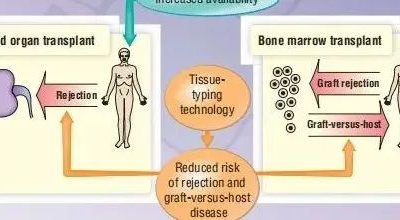

第二章介绍了免疫反应中有关细胞间相互作用和协作的基本概念。第7章和第8章解释了T细胞受体(TCR)只有在抗原提呈细胞(APC)上的主要组织相容性复合物(MHC)分子呈递抗原时才能识别抗原,这是通过细胞间相互作用启动免疫反应的一个例子。此外,为了充分激活B、T淋巴细胞,需要通过与其他细胞的相互作用提供共刺激信号,这一点在第11章中有所介绍,并在第15章中进一步进行了讨论。如上图,解释了细胞间的相互作用在产生效应B细胞(浆细胞)和效应T细胞(T辅助细胞和细胞毒性T淋巴细胞)所需信号中发挥着关键作用。本章也将讨论如何通过特定的免疫反应来对抗不同类型的病原体。